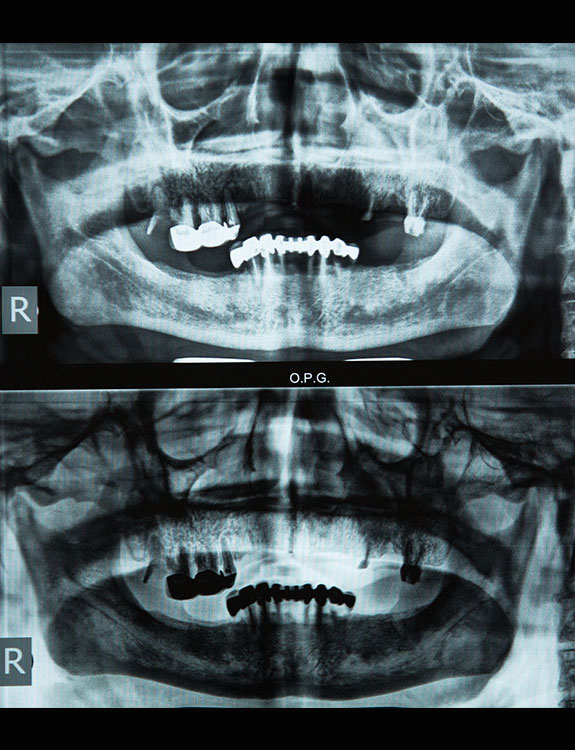

Dental implants are artificial tooth roots made of medical-grade titanium that are surgically placed into the jawbone. Once the implant integrates with the bone, a crown is fixed on top, giving you a strong, natural-looking replacement tooth.

When compared to bridges or dentures, dental implants offer unmatched comfort and longevity.